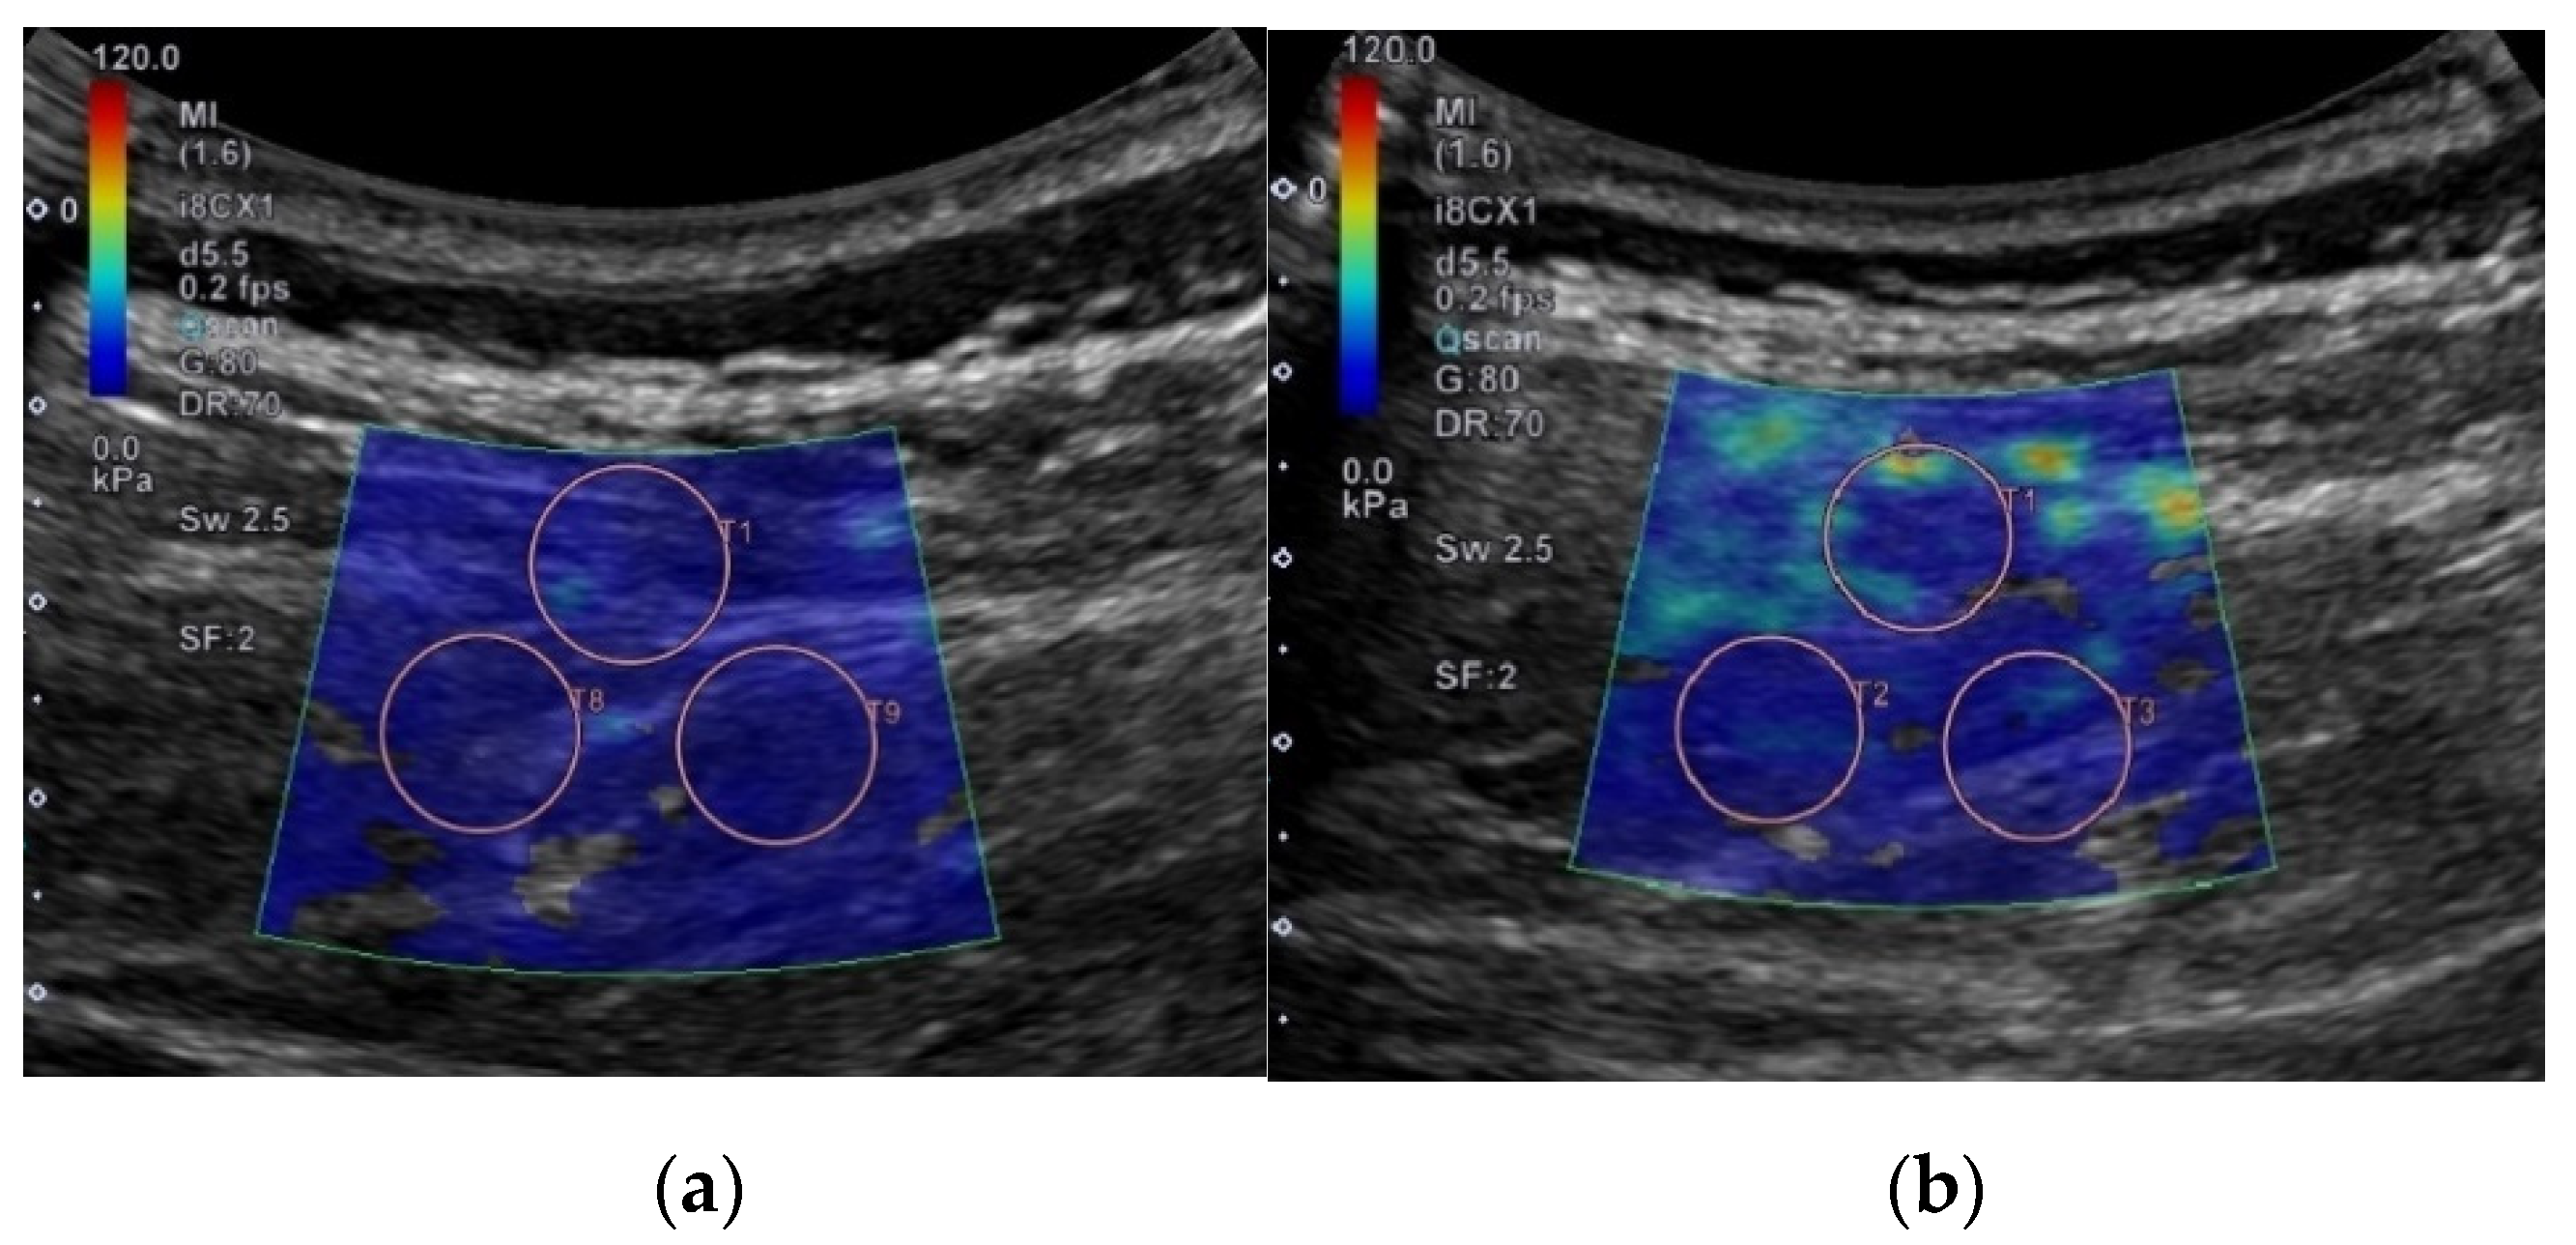

2.3. Ultrasound Measurement